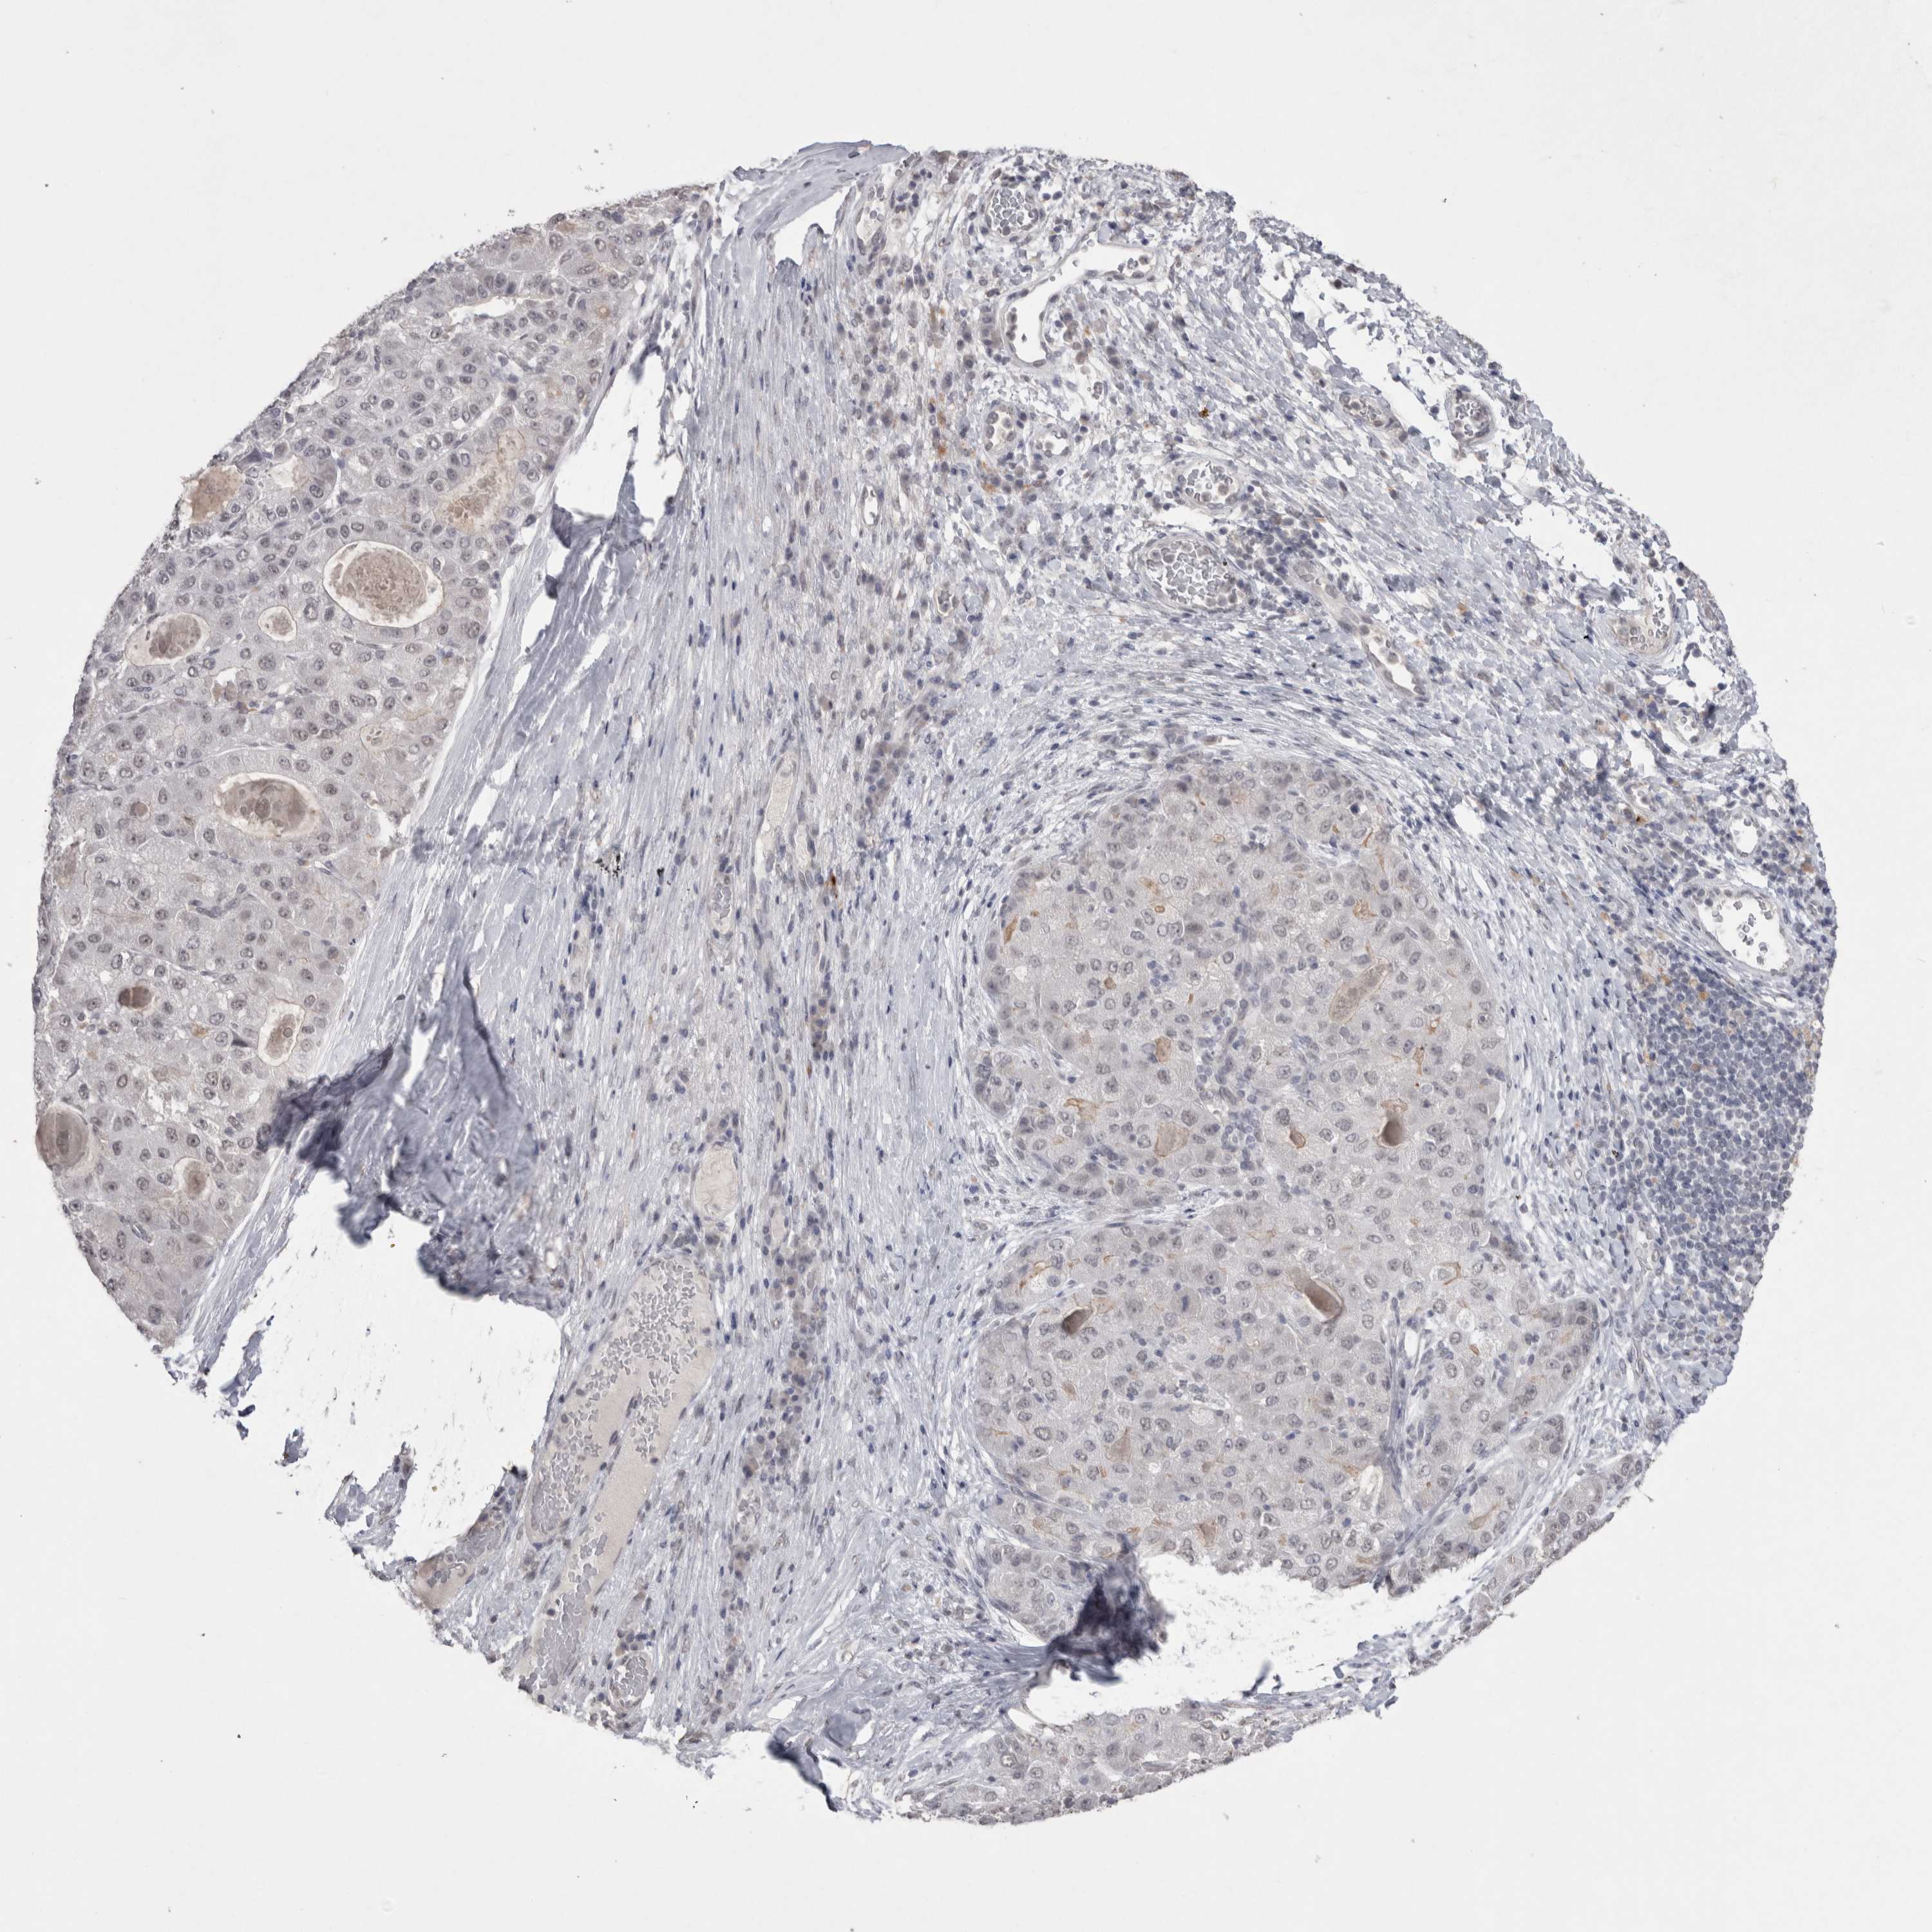

LIVER CANCER - Protein expressioni

A mouse-over function shows sample information and annotation data. Click on an image to view it in a full screen mode. Samples can be filtered based on level of antibody staining by selecting one or several of the following categories: high, medium, low and not detected. The assay and annotation is described here.

Note that samples used for immunohistochemistry by the Human Protein Atlas do not correspond to samples in the TCGA dataset.

Antibody stainingi

Antibody staining in the annotated cell types in the current human tissue is reported as not detected, low, medium, or high, based on conventional immunohistochemistry profiling in selected tissues. This score is based on the combination of the staining intensity and fraction of stained cells.

Each image is clickable and will lead to virtual microscopy that enables deeper exploration of all samples and also displays staining intensity scores, fraction scores and subcellular localization as well as patient and tissue information for each sample.

Antibody HPA037763

Antibody HPA037764

Antibody CAB026170

Staining

High

Medium

Low

Not detected

Intensity

Strong

Moderate

Weak

Negative

Quantity

>75%

75%-25%

<25%

None

Location

Nuclear

Cytoplasmic/membranous

Cytoplasmic/membranous,nuclear

Cholangiocarcinoma

Carcinoma, Hepatocellular, NOS